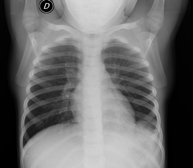

- RX Tórax

Una radiografía de tórax es una técnica mediante la cual, utilizando una pequeña dosis de radiación, se obtiene una imagen bidimensional de la caja torácica y su contenido (pulmones, corazón, mediastino, etc.). Es una de las pruebas médicas más comúnmente realizadas.